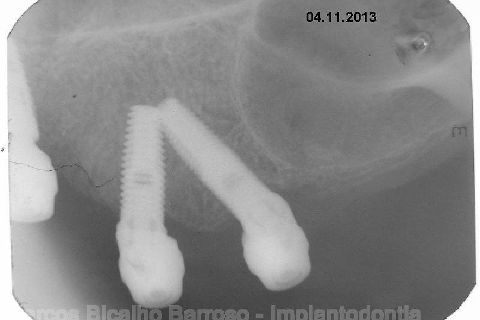

Atualização do caso clínico que já postei, "REABILITAÇÃO EM MAXILA ATRÓFICA COM IMPLANTES", um caso que inclui expansão do rebordo estreito com cinzel e martelo, expansores rosqueáveis, enxerto e instalação dos implantes distais inclinados tangenciando seio maxilar. Inclui esvaziamento do forame nasopalatino e preenchimento com biomaterial para instalação de dois implantes próximos dele. Cirurgia realizada em única sessão, com instalação dos 6 implantes. Para os colegas que não conheceram e/ou esqueceram da apresentação, este é o resumo do caso na fase cirúrgica.http://www.youtube.com/watch?v=BtvexFexRPA&hd=1